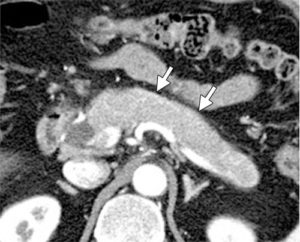

Панкреатит

При запаленні підшлункової залози у хворого присутня постійна печія, оперізуючий біль. У момент загострення хворого нудить, підвищується температура тіла. Після нудоти може з’являтися блювота з жовчю, що не приносить полегшення. Різке погіршення стану хворого вимагає негайного виклику швидкої медичної допомоги.